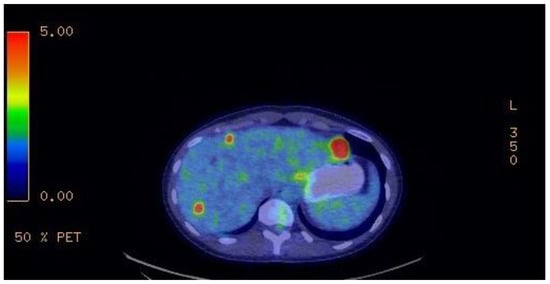

A 9-month follow-up FDG-TEP scan (Figure 4) after the introduction of imatinib showed disease progression with new liver metastasis. Therefore, sunitinib was started at the standard dose of 50 mg. Despite a 3-month course of this second-line treatment, further disease progression led us to initiate regorafenib at 160 mg. Unfortunately, the patient developed a severe morbilliform pancorporal rash 10 days after the introduction of regorafenib. She was treated with oral prednisone and her rash disappeared a few days later. Upon follow-up, once her skin rash resolved, a trial of 40 mg of regorafenib was tried. However, she developed a similar rash 4 h after taking the medication. Lastly, regorafenib was discontinued and ripretinib was started at 150 mg once a day. Her primary disease progressed at this usual dose, leading to a dose increase to 150 mg twice daily. The metastatic burden of her disease has remained stable under this fourth-line treatment for nearly a year at the current regimen. Her ongoing treatment is well tolerated. She has developed moderate palmoplantar hyperkeratosis induced by ripretinib, which is currently managed with topical treatment. Figure 5 summarizes the patient’s treatments.

Figure 4. Nine-month follow-up FDG-TEP scan after introduction of imatinib, showing disease progression with new liver metastasis.